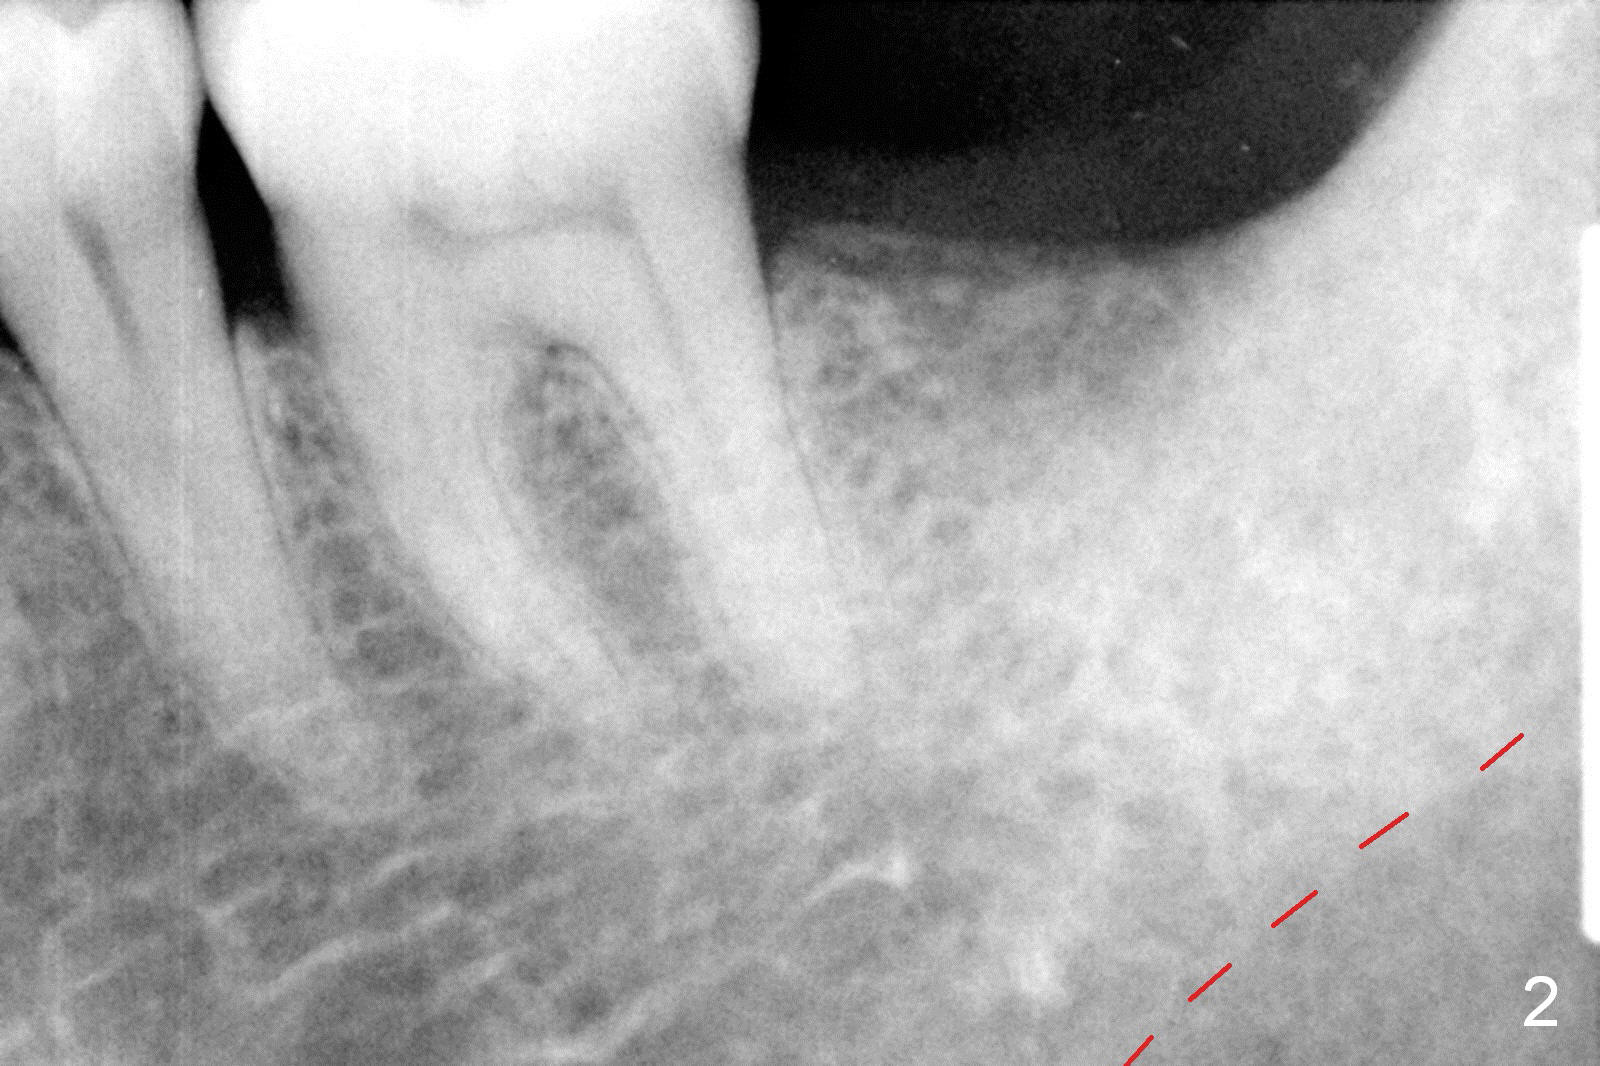

A 48-year-old lady is a dental phobic, requesting extraction of the lower left 2nd molar (Fig.1).   She returns for implant placement 9 months post extraction (Fig.2).  The ridge is mildly to moderately atrophic.  It appears that a 5x12 mm implant is appropriate for the site (Fig.3).  For safety, osteotomy is initiated at the depth of 10 mm; it appears that there is enough height for a 12 mm implant (Fig.4).  The depth is controlled by drill stopper (Fig.5 S).  Finally a 5x12 mm implant is apparently safely placed (Fig.6).  A healing abutment is placed and the incision is sutured with 4-0 Chromic gut (Fig.7).  Perio dressing is applied around the healing abutment for wound protection (Fig.8).  It appears that the healing abutment (Fig.8': *) helps stabilize the perio dressing, which remains in place 1 week postop.  When the perio dressing is removed, the wound around the healing abutment is healing (Fig.9).  There is no bone loss around the implant 3 months postop (Fig.10 (H: healing abutment), or 16 months postop (i.e., 9 months post cementation, Fig.11,12).  The patient complains of pain when she chews with the implant crown, but pain stops whenever she does not bite.  Percussion does not elicit any discomfort.  The gingiva is healthy.  There is possibility of the buccal plate being thin or the lingual plate being perforated in the submandibular fossa.  If the discomfort remains the same next 6 months, CBCT will be prescribed.